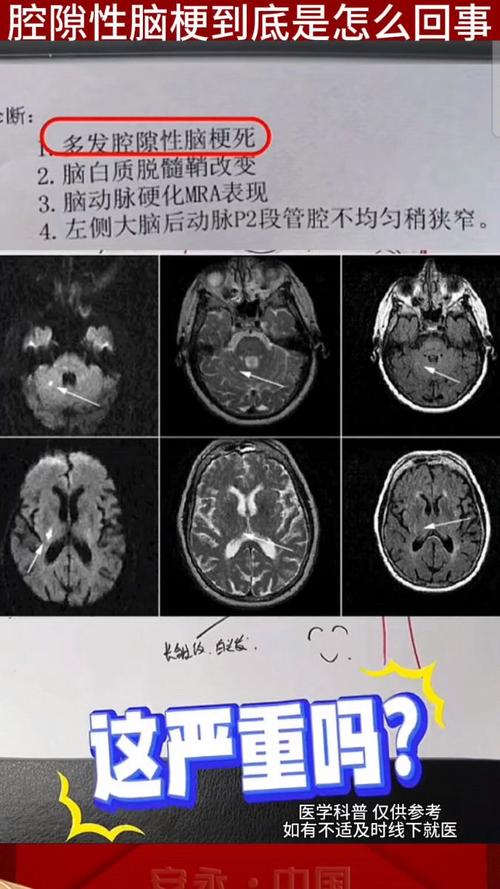

“腔梗”是“腔隙性脑梗死”(Lacunar Infarction)的简称。

- “腔隙”:指的是大脑深部直径在1.5到2毫米以下的小血管,它们就像树梢最细小的分支,当这些小血管堵塞时,它所供应的脑组织区域就会缺血坏死,形成一个很小的“洞”或“腔隙”。

腔梗灶的本质就是由小血管堵塞引起的小面积脑梗死,你可以把它想象成城市里的一条毛细血管堵塞了,而不是主干道(大脑的主要动脉)堵塞。

基底节区是腔梗最高发的部位之一,当报告上写“双侧基底节区腔梗灶”,就意味着大脑两侧对称的基底节区域都出现了这种小血管堵塞造成的微小梗死。

- 从病灶本身看:单个或少数几个无症状的腔梗灶,其严重性远小于大面积脑梗(比如导致偏瘫、失语的那种),很多人做头颅检查偶然发现,自己毫无感觉。

- 从数量和位置看:如果腔梗灶数量非常多,或者分布在关键的功能区(如脑干、丘脑),即使单个很小,也可能累积效应导致认知功能下降、记忆力减退、步态不稳等问题。

- 从预示意义看:发现腔梗灶是一个重要的“预警信号”,它说明你的脑血管已经出现了病变,未来发生更严重脑卒中(如大面积脑梗或脑出血)的风险显著增加。